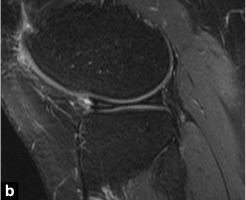

Le ménisque discoïde est une malformation congénitale rare du ménisque.Cette dysplasie méniscale touche presque exclusivement le ménisque latéral.Son diagnostic 'académique' en IRM repose sur la visualisation de la continuité des cornes antérieure et postérieure sur des clichés sagittaux en au moins 3 coupes consécutives de 5 mm d'épaisseur (Fig. 2).Ces résultats sont ajustés en fonction des paramètres partiels utilisés.

Figure 2 Ménisque latéral discoïde.Image sagittale pondérée en T1.Continuité des angles avant et arrière sur 3 profilés fixes consécutifs de 5 mm.Notez la dégénérescence myxoïde de la corne antérieure de ce ménisque discoïde.